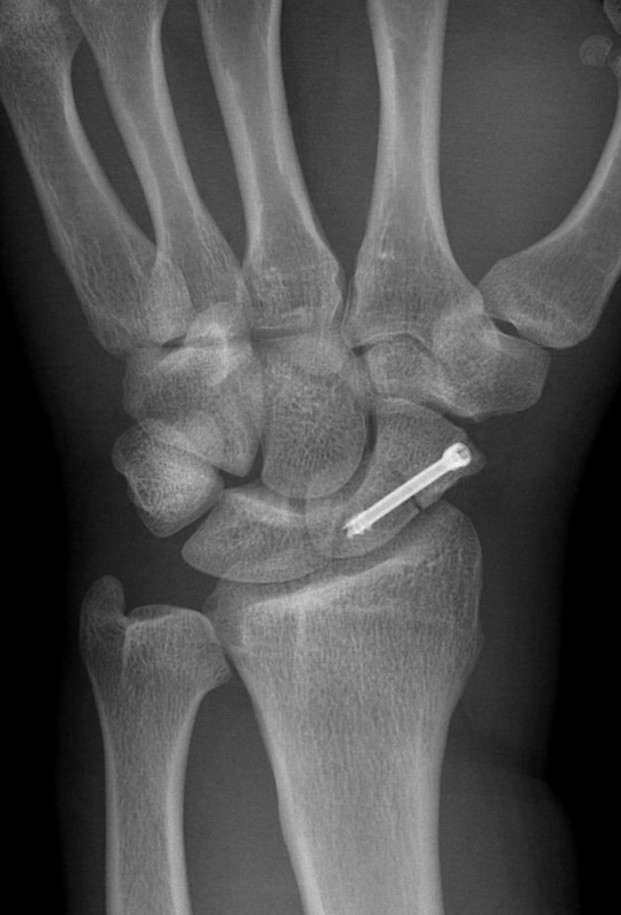

Feldman G, Orbach H, Rozen N, Rubin G. Usefulness of prophylactic antibiotics in preventing infection after internal fixation of closed hand fractures. Hand Surg Rehabil 2021;40(2):167-70.

Abul A, Karam M, Al-Shammari S, Giannoudis P, Pandit H, Nisar S. Peri-operative antibiotic prophylaxis in K-wire fixation: a systematic review and meta-analysis. Indian J Orthop 2023;57(7):1000-7.

Ridley TJ, Freking W, Erickson LO, Ward CM. Incidence of treatment for infection of buried versus exposed Kirschner wires in phalangeal, metacarpal, and distal radial fractures. J Hand Surg Am 2017;42(7):525-31.